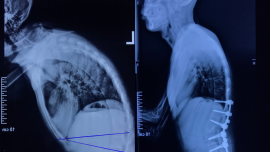

第一期:无声的预警——认识中老年脊柱骨折 人体的脊柱如同房屋的顶梁柱,由颈椎、胸椎、腰椎、骶骨和尾骨连接而成,不仅支撑着我们的身体,还保护着重要的脊髓神经。许多人认为骨折必定源于严重外伤,但对中老年人来说,情况可能大不相同。 脊柱骨折是一种常见的脊柱损伤,尤其好发于胸腰段。随着年龄增长,骨骼中的矿物质会悄然流失,导致骨质疏松,骨骼的抗压能力减弱。这时,即使是一个轻微的外力——比如不小心坐倒在地、弯腰提重物,甚至剧烈的咳嗽——都可能使椎体逐渐被挤压,形成压缩性骨折。这也是许多老年人出现身高变矮、驼背加重的重要原因。 此外,某些疾病如肿瘤、糖尿病、类风湿关节炎等,也会让骨骼变得脆弱,更容易发生"病理性骨折"。 如果您或家中的长辈出现以下情况,建议及时关注: 没有明显外伤,但腰背部持续疼痛,尤其在翻身、起床时加重; 身高较年轻时明显降低(超过3厘米),或驼背程度日益加重; 轻微活动后即感到背部不适,休息后仍不缓解。 这些可能是脊柱发出的"求助信号"。建议尽早就医,通过X光、CT或骨密度等专业检查明确原因。早期发现是避免严重并发症的关键。 第二期:危险因素揭秘——脊柱骨折更"偏爱"谁? 脊柱骨折的发生,往往并非偶然。了解其背后的危险因素,有助于我们更好地识别风险,及早预防。 脊柱骨折主要"偏爱"以下五类人群: 1.中老年人,尤其是绝经后女性; 2.骨质疏松患者; 3.长期服用糖皮质激素者; 4.患有某些慢性疾病; 5.有骨折家族史或既往发生过骨折。 定期进行骨密度检查,是评估骨骼健康状况、及早发现风险的有效方式。建议高危人群每年检查一次,普通人群65岁后也应定期筛查。 第三期:防患于未然——脊柱骨折的日常预防指南 预防脊柱骨折,尤其是对于骨骼开始变得脆弱的中老年人来说,是守护晚年生活质量的关键。以下五大措施,帮助您有效筑牢骨骼"防线": 1.营养支持:补足钙与维生素D 钙是骨骼的"砖石"。推荐每日摄入1000-1200mg。 优质来源:牛奶、酸奶、豆制品、绿叶蔬菜(如西蓝花)、芝麻酱。 维生素D是帮助钙吸收的"钥匙"。老年人日晒不足,极易缺乏。 优质来源:海鱼(三文鱼、沙丁鱼)、蛋黄、动物肝脏。必要时在医生指导下服用补充剂。 2.谨慎用药:避开"骨骼杀手" 严格遵医嘱使用糖皮质激素,切勿自行长期、大剂量服用。 积极控制糖尿病、类风湿等慢性疾病,定期复查。 3.科学运动:强肌健骨 推荐运动:散步、太极拳、游泳等低强度运动,能增强腰背部肌肉力量,更好地保护脊柱。 注意事项:避免剧烈扭转、跳跃和提重物。运动量以身体舒适、不感到疲劳为宜。 4.定期监测:掌握骨骼动态 建议65岁以上女性和70岁以上男性定期进行骨密度检查。 高危人群应提前至40岁以后就开始监测。 第四期:科学应对——脊柱骨折的治疗与康复 一旦发生脊柱骨折,科学规范地治疗是恢复功能、避免严重后果的关键。现代医学的进步已让治疗方案更加安全有效。 治疗方法主要根据骨折严重程度和是否损伤神经来决定: 保守治疗  适用对象:轻度、稳定的压缩性骨折(椎体高度压缩未超过1/3),且无神经损伤症状。 治疗方式:短期卧床休息、佩戴特制支具固定、药物镇痛以及循序渐进的康复理疗。 核心目标:为骨骼自然愈合创造稳定环境,同时避免长期卧床引发肺炎、血栓等并发症。 手术治疗 适用对象:骨折严重、脊柱不稳定或已压迫脊髓神经(出现肢体麻木、无力、大小便困难等症状)的患者。 主流技术:目前多采用微创手术,如椎体成形术。医生会向被压扁的椎体内注入少量"骨水泥",将其快速撑起并固定。 巨大优势:创伤小、疼痛缓解快(术后一两天即可在护具保护下床活动)、极大缩短卧床时间,特别适合不能耐受大手术的老年患者。 髓损伤是脊柱骨折最严重的并发症,可能导致瘫痪且恢复困难。若怀疑或确诊脊柱骨折,应立即前往正规医院就诊,由专业医生制定个性化治疗方案,切勿因恐惧手术而延误治疗或选择长期卧床。 第五期:长期管理——避免二次骨折的关键 脊柱骨折治疗结束后,仍需长期关注骨骼健康,以预防再骨折并提高生活质量。忽视后续管理可能导致以下后果: 慢性疼痛:骨折部位愈合不佳或脊柱力线改变,可能导致疼痛迁延不愈,影响日常生活。 再发骨折风险极高:一次骨折已表明骨骼质量差,其他部位(如髋部、手腕)发生骨折的风险显著增加。 脊柱畸形:多个椎体骨折会导致身高严重缩短、驼背加剧,甚至影响心肺功能。 神经功能损害:后期仍可能出现下肢麻木、步态不稳等问题。 因此,我们建议建立长期健康管理计划: 1.坚持抗骨质疏松治疗:这是预防再骨折的关键措施。在医生指导下,持续服用抗骨质疏松药物,并补充钙和维生素D,增强骨骼。 2.系统康复训练:在康复治疗师的指导下,进行核心肌力、平衡和柔韧性训练,为脊柱建立强大的“肌肉护甲”。 3.定期复查与随访:定期到骨科复查X光、CT或骨密度,评估愈合情况和骨量变化,及时调整治疗方案。 结语 守护脊柱健康是一项终身事业。对于中老年人而言,了解风险、积极预防、及早就医、科学治疗和坚持管理,是应对脊柱骨折、安享健康晚年的完整策略。请用心关爱您的身体支柱,让它继续坚强地支撑您的美好生活。 脊柱外科简介 北京大望路急诊抢救医院(原北京朝阳急诊抢救中心)脊柱外科,是从事脊柱疾病临床研究的专业科室,有着雄厚的人才资源和各种诊断治疗所需的高端设备,科室崇尚精诚、精益、精心的工作精神,全心全意为患者服务是科室的宗旨。在夏庆福主任的带领下,形成了以脊柱创伤、内镜微创技术、脊柱矫形、复杂脊柱疾病的诊治等方面为特色的专科。目前科室拥有床位51张,副主任医师5人,主治医师3人,住院医师8人,护理人员16人。  专家简介 夏庆福 副主任医师 脊柱外科主任 武警辽宁省总队医院骨科原主任、武警辽宁省消防医院原业务院长,任辽宁省脊柱脊髓损伤学会常任理事。毕业于哈尔滨医科大学,多次参加国内学术交流,于北京积水潭医院创伤、脊柱、矫形及手外科学习2年余,擅长对、脊髓损伤、复杂创伤骨科病的治疗,能独立完成关节置换及脊柱、创伤骨科病等各类手术。先后在国内学术期刊发表学术文章20余篇。 学术任职: 中国修复重建专业委员会、辽宁省脊柱脊髓损伤协会委员、中国老年学和老年医学学会第四届常务委员兼执行干事; 北京慢性病防治与健康教育研究会脊柱侧弯专业委员会副主任委员兼秘书长; 北京慢性病防治与健康教育研究会脊柱外科专业委员会常务委员; 中国残疾人康复协会肢体残疾康复专业委员会委员; 北京医师协会骨科专科医师分会委员; 中国非公立医疗机构协会委员; 中国老年保健医学研究会老年骨与关节病分会委员; 黄立军 副主任医师 脊柱外科副主任 擅长脊柱创伤、脊柱退变性、四肢创伤等疾病的诊断与治疗,包括颈椎病、颈椎管狭窄症、颈椎后纵韧带骨化、胸椎黄韧带骨化、腰椎管狭窄、腰椎间盘突出、腰椎滑脱,各类脊柱骨折。 学术任职:中国非公立医疗机构协会委员 张玉双 副主任医师 脊柱外科副主任 擅长脊柱畸形、脊柱创伤、脊柱退变性、四肢创伤等疾病的诊断与治疗,包括特发性脊柱侧弯、重度脊柱侧弯、强直性脊柱炎性脊柱后凸、颈椎病、颈椎管狭窄症、颈椎后纵韧带骨化、胸椎黄韧带骨化、腰椎管狭窄、腰椎间盘突出、腰椎滑脱,各类脊柱与四肢骨折。 方程 副主任医师 擅长脊柱骨折,颈肩疼、腰腿痛、颈椎病、颈椎管狭窄、腰椎间盘突出、腰椎管狭窄症等疾病的诊断和治疗。 王建国 副主任医师 擅长脊柱损伤及疾病的诊断与治疗;微创技术在脊柱外科的应用;骨质疏松骨折的微创诊疗。 科室基本情况 脊柱外科主要特点是高精尖技术和微创治疗,诊治范围包括: 各类脊柱骨折及脊髓损伤 颈椎病及颈椎间盘突出症 颈椎后纵韧带骨化症 胸椎管狭窄症 腰椎间盘突出症和管狭窄症 腰椎峡部裂与滑脱症 老年性骨质疏松症 脊柱侧弯、强直性脊柱炎、脊柱结核和肿瘤 急性腰扭伤、腰肌劳损、肌筋膜炎和椎间盘源性腰痛 手术方式包括传统手术和新开展的微创手术,如椎间盘镜下摘除术、经皮置钉手术等。这些治疗方法有效减少了患者的痛苦和经济负担,取得了良好的社会效果 使用的先进设备包括: 天玑骨科手术机器人 3D C型臂 计算机导航 碳素手术床 术中神经电生理监测 超声骨刀 微创高速磨钻 多功能显微镜 椎间孔镜 关节镜等。 科室技术特色优势 脊柱微创: 1. 经皮椎间孔镜技术(PELD):科室开展的经皮椎间孔镜技术,在腰椎间盘突出症、颈椎病、胸椎管狭窄等疾病的治疗上取得了良好疗效。该技术仅约6毫米切口,一针缝合,手术风险低、成功率高、并发症少、疗效显著。 2.经皮椎体后凸成形术(PKP):科室在PKP处理不同年龄段脊柱骨折患者方面积累了丰富的手术经验,特别是高龄重症老年患者压缩性骨折的治疗。 3.微创OLIF。 4.微创MIDLIF。 5.经皮内固定术。 脊柱高难度手术: 1.上颈椎高难度手术:寰枢椎,又称为上颈椎,是人体生命的中枢所在,该区域的手术难度大、风险高。脊柱外科医师团队已顺利开展该技术。 2.严重胸腰椎骨折脱位后路手术。 3.后路侧块螺钉手术。 4.颈椎人工间盘置换术。 脊柱肿瘤: 骶骨神经鞘瘤手术。 脊柱侧弯: 1.头、盆环牵引治疗重度脊柱畸形。 2.脊柱侧弯畸形矫正:对于高发的脊柱侧弯疾病,先进行科学评估,利用三维CT重建进行术前规划,术中采用脊髓电生理监测,超声骨刀、三维C臂等先进设备应用为手术保驾护航,提高手术安全性,真正实现高难度、高风险手术常规化。多种技术设备辅助精准置钉,帮助患者“挺起脊梁”。  3.V形截骨治疗强直性脊柱炎性脊柱后凸(AS)。 4. 休门氏病的手术治疗。 5. 结核性后凸的手术治疗。 脊柱常规疾病的手术治疗: 1.腰椎间盘突出后路手术。 2.腰椎滑脱手术。 脊柱感染: 复杂脊柱感染疾病治疗个性化:脊柱结核、脊柱炎症是导致长期慢性腰背疼痛的常见病因,通过规范化、标准化的抗菌方案,有效遏制炎症,促进早期康复。 脊柱外科咨询电话:010-5963 2198/1800138****。